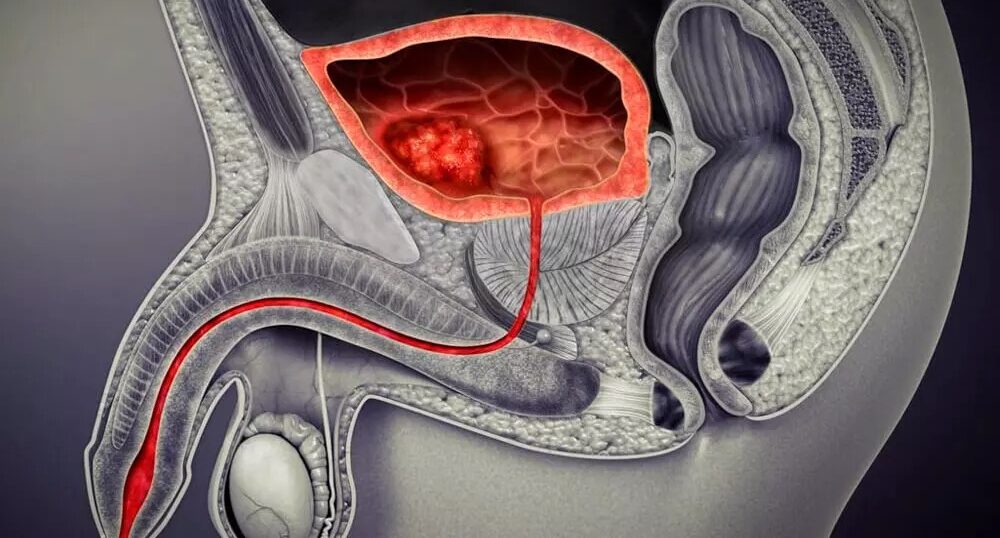

La uretromeatotomía es un procedimiento quirúrgico ambulatorio que se realiza para ampliar el meato uretral y el segmento distal de la uretra cuando existe una estrechez que dificulta la salida normal de la orina 🚻

🏥 ¿Cómo se realiza?

El objetivo es eliminar la obstrucción y restablecer un flujo urinario adecuado.

⚠️ La evaluación especializada es clave para confirmar el diagnóstico y descartar otras causas de obstrucción urinaria.